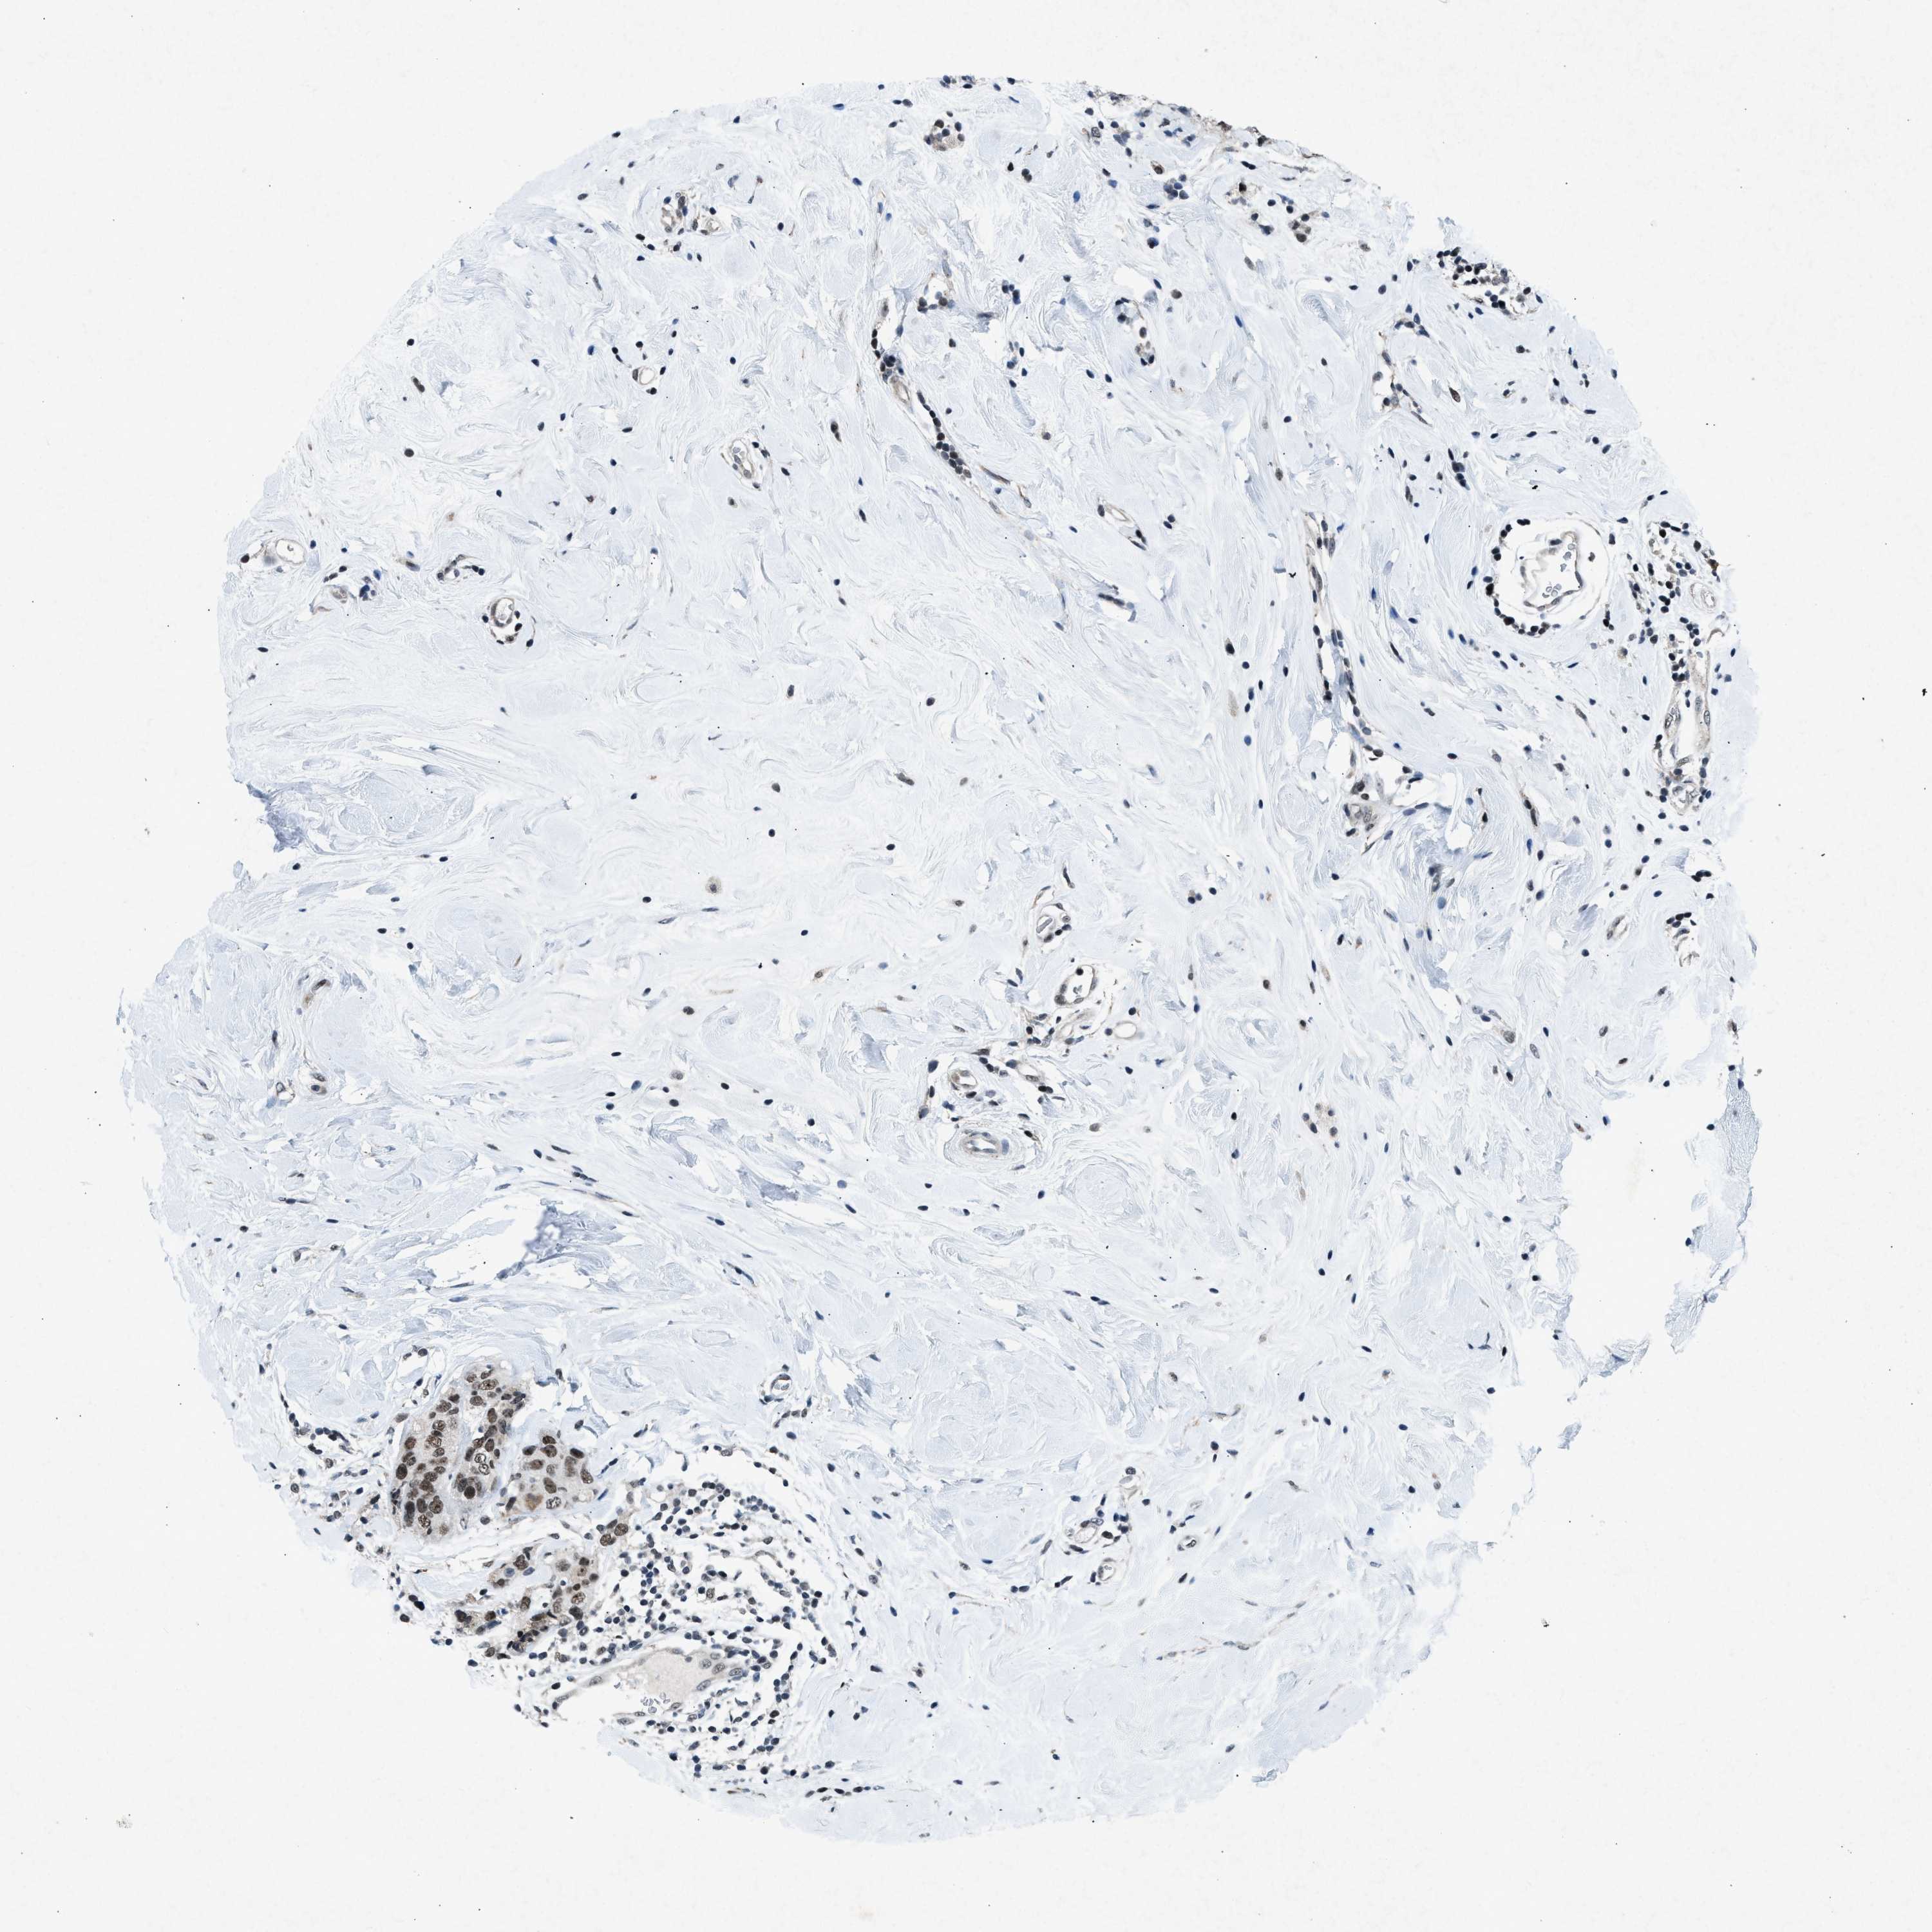

BRCA TCGA BRCA VALIDATION PROTEIN EXPRESSION